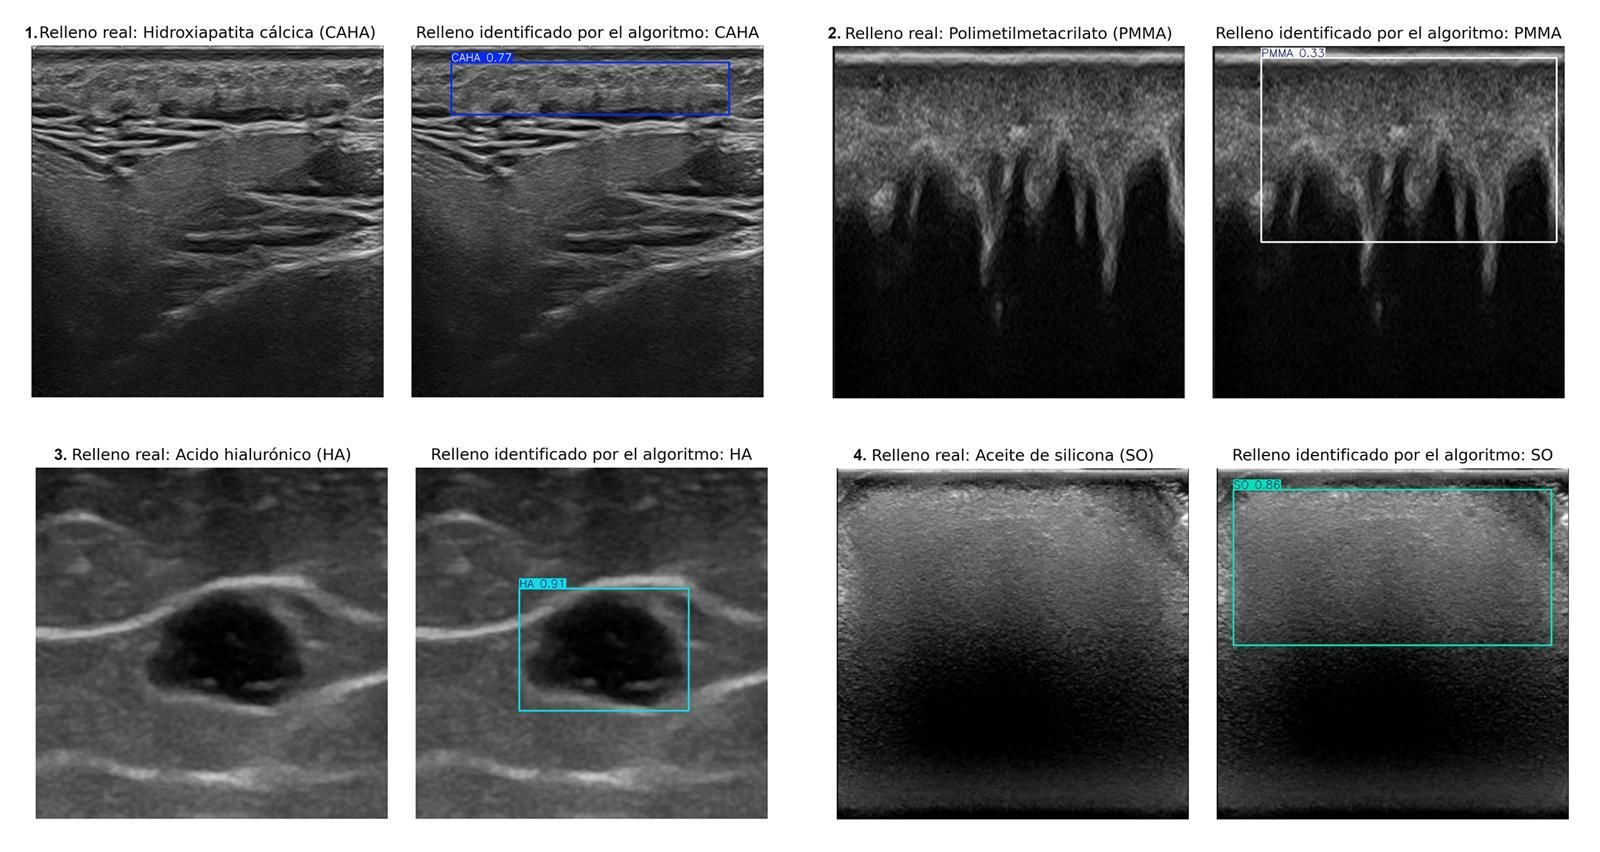

Imagen remitida por la UGR sobre este sistema de IA que permite identificar rellenos estéticos.

Un estudio internacional llevado a cabo por investigadores de las universidades de Granada y Chile ha desarrollado un sistema de inteligencia artificial capaz de identificar automáticamente cuatro tipos de rellenos estéticos en imágenes ecográficas.

El equipo de investigación dirigido por la doctora Ximena Worstman de la Universidad de Chile, que ha contado con la decisiva participación de los profesores del Departamento de Ciencias de la Computación e Inteligencia Artificial de la Universidad de Granada Manuel Lozano y Francisco J. Rodríguez, ha creado un sistema de inteligencia artificial basado en aprendizaje profundo. Este algoritmo es capaz de identificar y discriminar automáticamente, en imágenes ecográficas, cuatro tipos de rellenos cosméticos: hidroxiapatita cálcica, ácido hialurónico, polimetilmetacrilato y aceite de silicona.